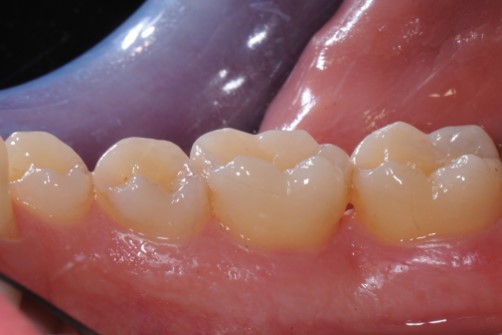

01/22 - Pre-surgical clinical situation, buccal view.

Deep intrabony defects treated using Straumann® Emdogain® - Dr. M. Stefanini